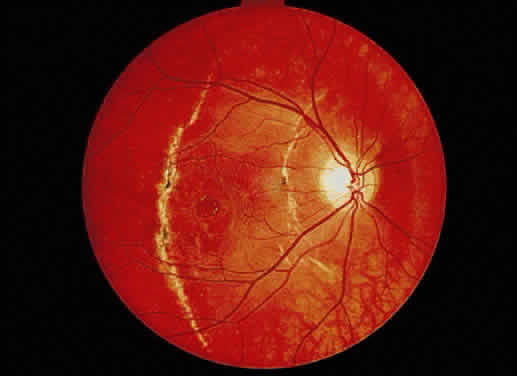

Fig. 51. A. Fundus photograph of retinitis pigmentosa with bone spicule pigmentation. The “bone-corpuscular” appearance is the result of pigment

epithelial melanin accumulation around the small retinal vessel branches. B. Advanced retinitis pigmentosa. There is marked pigment clumping along

with waxy pallor of the disc and attenuated arterioles. Fig. 51. A. Fundus photograph of retinitis pigmentosa with bone spicule pigmentation. The “bone-corpuscular” appearance is the result of pigment

epithelial melanin accumulation around the small retinal vessel branches. B. Advanced retinitis pigmentosa. There is marked pigment clumping along

with waxy pallor of the disc and attenuated arterioles.